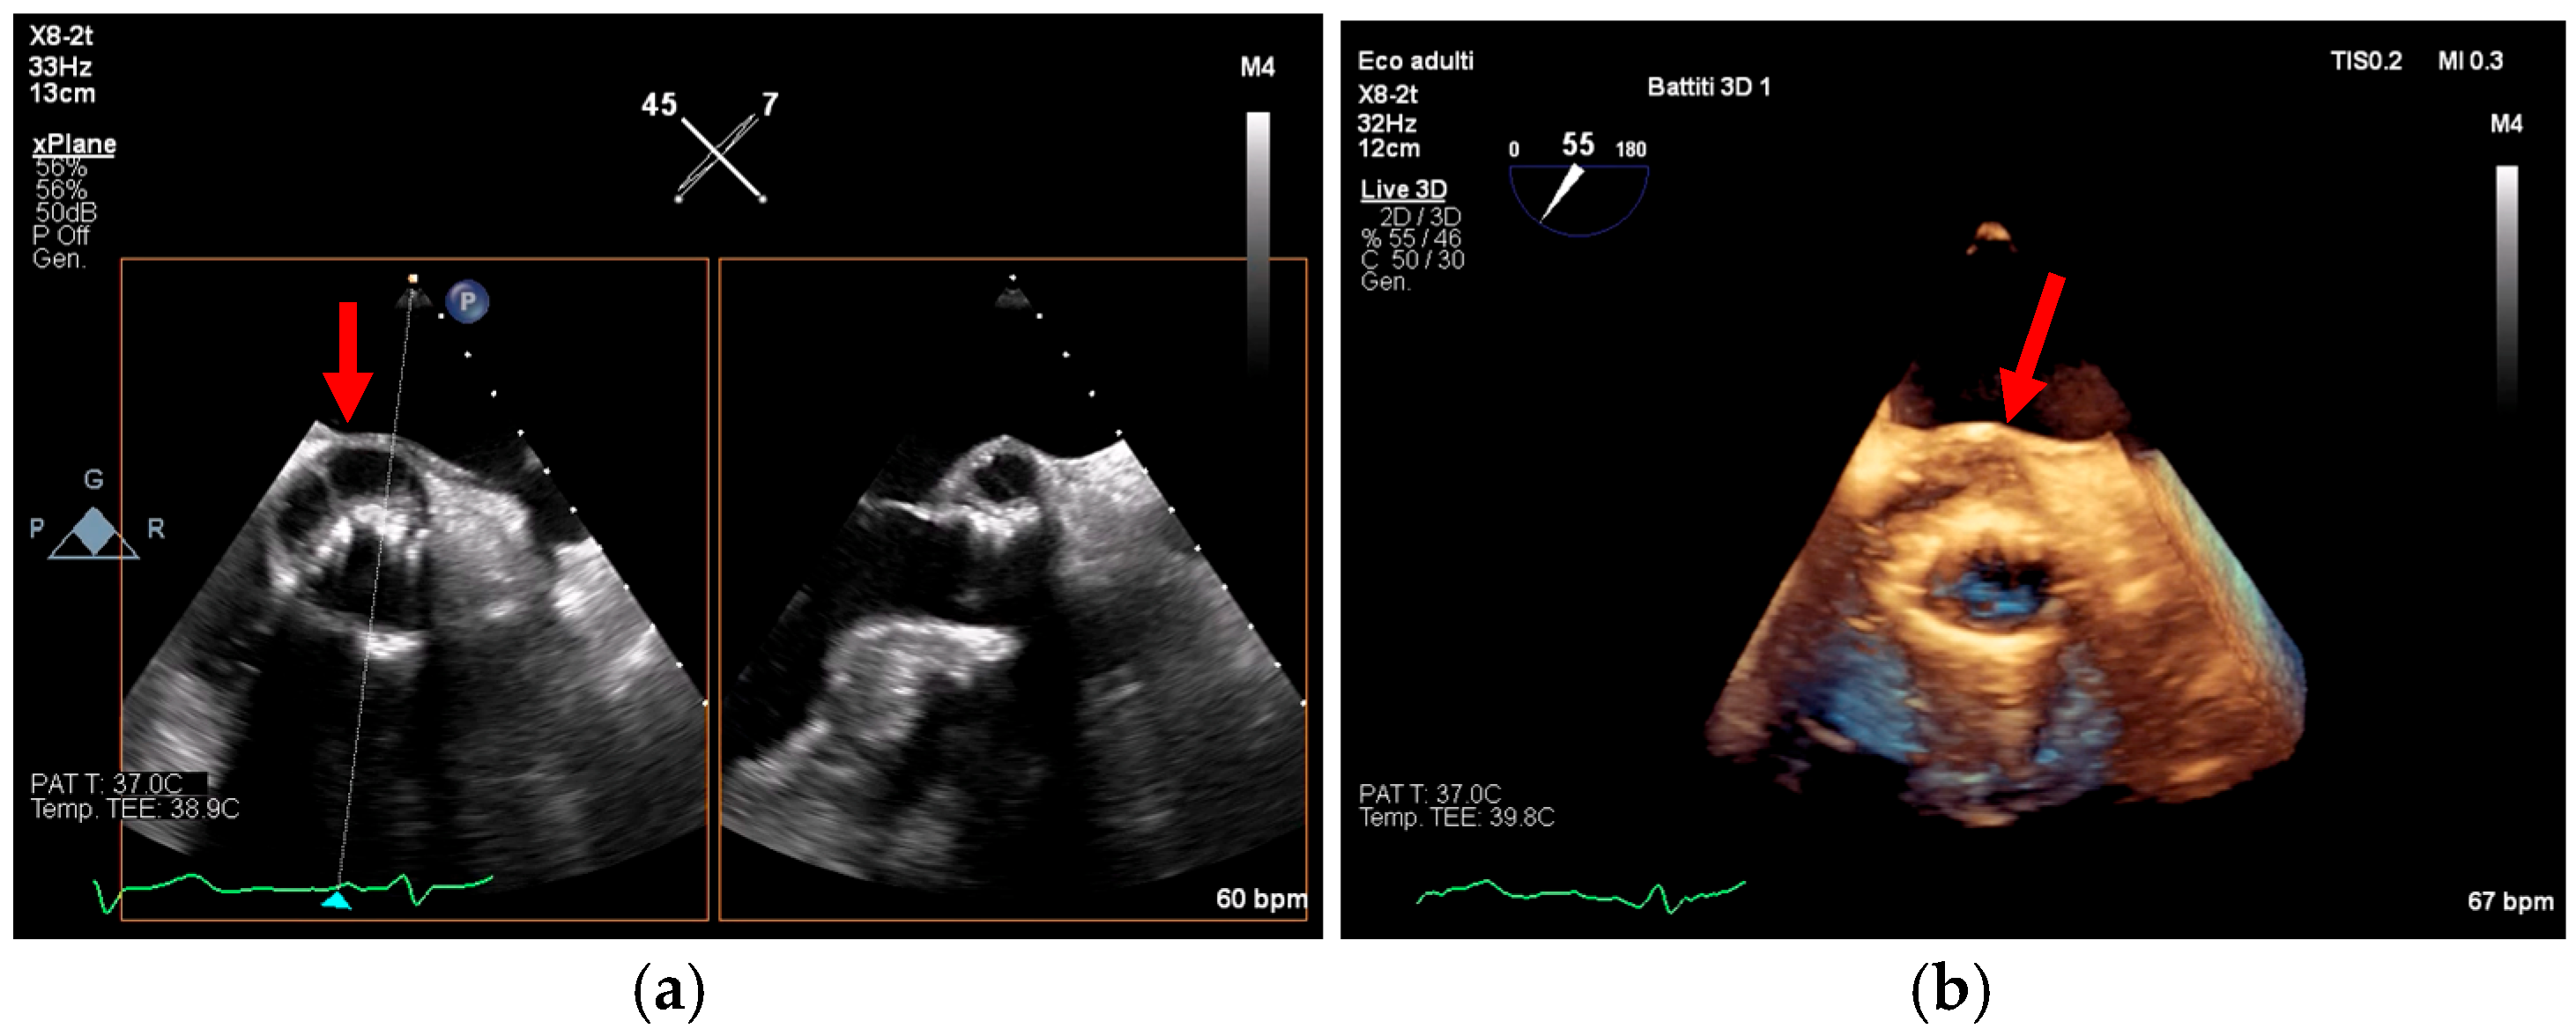

Advanced Imaging in Cardiac Implantable Devices

- Poterała, M.; Kutarski, A.; Brzozowski, W.; Tomaszewski, M.; Gromadziński, L.; Tomaszewski, A. Echocardiographic assessment of residuals after transvenous intracardiac lead extraction. Int. J. Cardiovasc. Imaging 2020, 36, 423–430. [Google Scholar] [CrossRef]

- Narducci, M.L.; Di Monaco, A.; Pelargonio, G.; Leoncini, E.; Boccia, S.; Mollo, R. Presence of ‘ghosts’ and mortality after transvenous lead extraction. Europace 2016, 19, 432–440. [Google Scholar] [CrossRef][Green Version]

- Le Dolley, Y.; Thuny, F.; Mancini, J.; Casalta, J.-P.; Riberi, A.; Gouriet, F. Diagnosis of Cardiac Device–Related Infective Endocarditis After Device Removal. JACC Cardiovasc. Imaging 2010, 3, 673–681. [Google Scholar] [CrossRef]

- Li, Y.; Jiang, L.; Wang, L.; Han, Q.; Yin, X.; Feng, Y. Ghost in the right atrium: A case report on successful identification of residual fibrous tissue. Heliyon 2023, 9, e21982. [Google Scholar] [CrossRef] [PubMed]

- Dilsizian, V.; Budde, R.P.J.; Chen, W.; Mankad, S.V.; Lindner, J.R.; Nieman, K. Best Practices for Imaging Cardiac Device–Related Infections and Endocarditis. JACC Cardiovasc. Imaging 2022, 15, 891–911. [Google Scholar] [CrossRef] [PubMed]